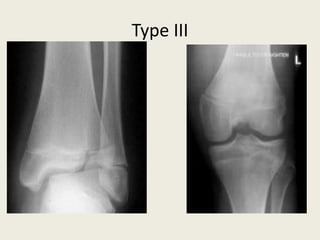

• Accounts for 8% of all physeal injuries.

• Transverse fracture through the growth plate and a vertical fracture through

the epiphysis.

• Type III injuries are more commonly seen in older children where the

growth plates have started to close. It is a combination of a horizontal

fracture line through the physis and a vertical fracture line which runs from

the growth plate through the epiphysis to the articular surface.

• Displaced injuries may result in a physeal bar, leading to growth disturbance

and joint incongruity, leading to arthritis.

• Most displaced type III injuries require open reduction internal fixation

(ORIF).

TypeIII

Type III